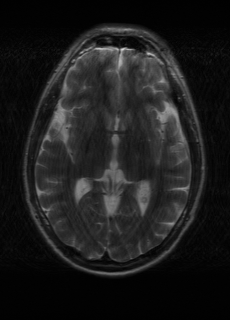

As we observe from the right image in Fig. 2, our BRM, both from MIMO and SISO settings, predicts the performance of dedicated models with a high correlation. We further choose the best three , and perform the last stage of fine-tuning accordingly to (6). A visual evaluation on real data is shown in Fig. 3. For simulated data, please refer to the Supplemental Material section.

Base on the best performing , we perceive that among , , and FLAIR, the results are best when is sampled the most. We suggest that this makes intuitive sense as images provide the best contrast out of the three sequences, which can compensate for the details lost in other images. The same observation can be made on the simulated data, where both and FLAIR show good contrast. When the time setting is changed to non-uniformity, we can see that our search for the best sampling strategy reflects the change. is sampled more as a result of faster acquisition time, while is still sufficiently sampled.

| Sequence | LR | SISO | MIMO | MIMO tuned | GT |

|---|---|---|---|---|---|

(a) 34.38/0.9371

(a) 34.38/0.9371

|

(b) 42.42/0.9883

(b) 42.42/0.9883

|

(c) 44.60/0.9920

(c) 44.60/0.9920

|

(d) 45.50/0.9940

(d) 45.50/0.9940

|

(e) PSNR/SSIM

(e) PSNR/SSIM

|

|

(f) 29.74/0.8903

(f) 29.74/0.8903

|

(g) 36.25/0.9734

(g) 36.25/0.9734

|

(h) 36.42/0.9752

(h) 36.42/0.9752

|

(i) 37.70/0.9832

(i) 37.70/0.9832

|

(j) PSNR/SSIM

(j) PSNR/SSIM

|

|

(k) 39.89/0.9311

(k) 39.89/0.9311

|

(l) 43.94/0.9864

(l) 43.94/0.9864

|

(m) 44.74/0.9883

(m) 44.74/0.9883

|

(n) 45.49/0.9894

(n) 45.49/0.9894

|

(o) PSNR/SSIM

(o) PSNR/SSIM

|